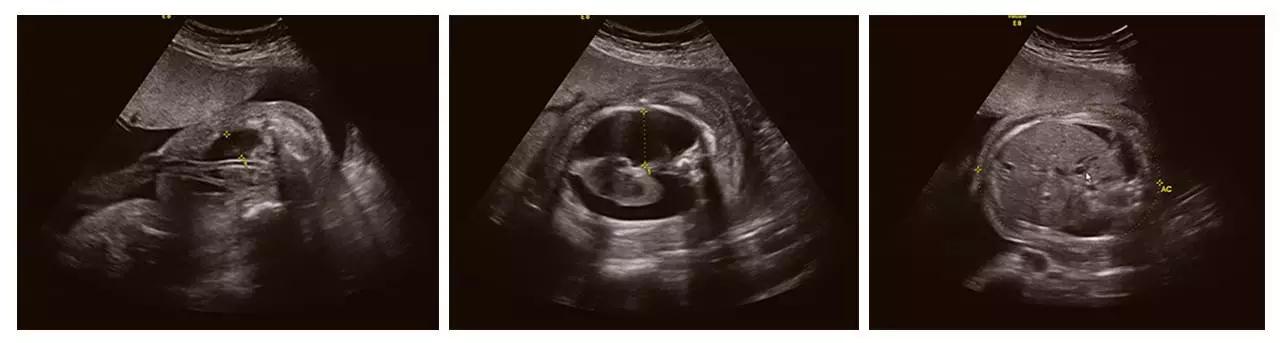

(胎儿左手未见,考虑截肢畸形)

(胎儿颅内结构异常、眼距窄、鼻结构异常...)